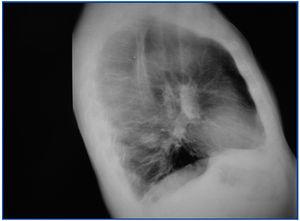

Inicia tratamiento conservador con IECA y ARAII. Al cuarto mes del diagnóstico, por ausencia de respuesta, se inicia CsA sin éxito. Al sexto mes, se cambia el tratamiento a clorambucil y prednisona manteniéndose durante ocho meses sin obtener respuesta y suspendiéndose por leucopenia. Al año y medio posbiopsia se objetiva remisión parcial (proteinuria: 5 g/día) con tratamiento conservador. A los dos años aparece un nódulo en el lóbulo pulmonar inferior izquierdo (figura 1). La fibrobroncoscopia confirma carcinoma epidermoide en estadio IV. El estudio de extensión muestra numerosos nódulos compatibles con metástasis pleurales, óseas y hepáticas.

Figura 1. Radiografía lateral de tórax